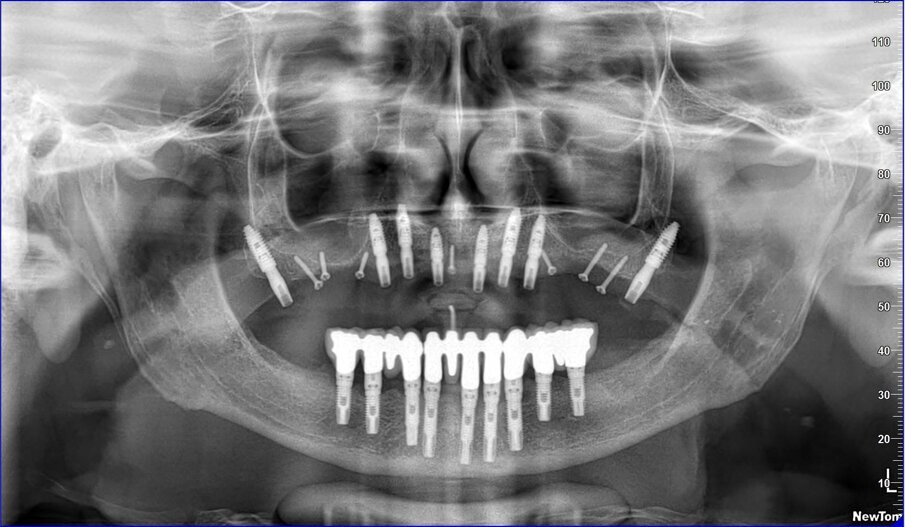

Gli impianti vengono distribuiti lungo tutta l’arcata cercando il parallelismo e limitando il più possibile i cantilever (6-7 impianti superiori e 5-6 impianti inferiori). La scelta di utilizzare i monconi dritti (grazie al parallelismo degli impianti) è da preferire in quanto quest’ultimi sono anche i più robusti e resistenti nel tempo al carico assiale; inoltre caricano l’impianto lungo il suo asse limitando i carichi disassati. Una volta elevato il lembo mucoperiosteo ed evidenziato l’osso alveolare o basale, attenzione deve essere fatta nel fare un’ostectomia riduttiva mediante una fresa a palla del diametro di 0,6-0,8 cm per creare un piano più uniforme possibile tale da formare una piattaforma d’osso alla stessa altezza, guadagnando anche spessore V-L ed uniformità. Gli impianti devono essere posizionati alla stessa altezza tra di loro e distanziati in maniera tale da favorire le manovre di igiene orale inter-implantare. Una volta posizionate le fixture sottocrestali (1-3 mm) come descritto, vanno connessi i monconi solitamente con collare mucoso di 3-4,5 mm in altezza, ponendo particolare attenzione che i tessuti molli suturati non coprano la parte di accoppiamento conometrico. Verificato il parallelismo corretto dei monconi mediante i pin parallelizzatori, siamo certi che l’accoppiamento e la disconnessione delle cappette contenute nella protesi potrà avvenire nel miglior modo possibile senza creare tensioni.

La resina alla stato ancora tenero va indurita con la lampada polimerizzante per alcuni minuti; una volta controllata la masticazione anche senza la chiave articolare e fatti gli opportuni minimi ritocchi, la protesi va rimossa e rifinita a dovere, poi riaccoppiata. Una OPT di conferma serve per verificare il corretto alloggiamento delle cappette sui monconi e la passività del manufatto.

Le tabelle 1-8 mostrano, su un totale di 313 impianti eseguiti tra arcata superiore (208) e inferiore (105), che la tecnica non ha alcuna complicanza biologica a 3 anni di esecuzione, non sono stati evidenziati fallimenti implantari in arcata inferiore (18 pazienti), solamente 5 in arcate superiori tutti nella zona molare (29 pazienti). In 1 paziente è stata registrata una frattura della protesi dovuta a eccessiva distanza tra gli impianti (zona laterale superiore e tuberosità) con antagonista naturale senza presenza di molari; 3 fratture dei denti in pazienti con bruxismo e serramento; circa la metà dei casi (140 impianti) è stata eseguita in condizione post-estrattiva e alcuni casi sono stati caricati con metodiche avanzate di rialzo di seno mascellare (11 pazienti) e 1 con Split Crest. Tutti gli impianti sono stati caricati immediatamente, anche quelli nei settori posteriori superiori o nella tuberosità.